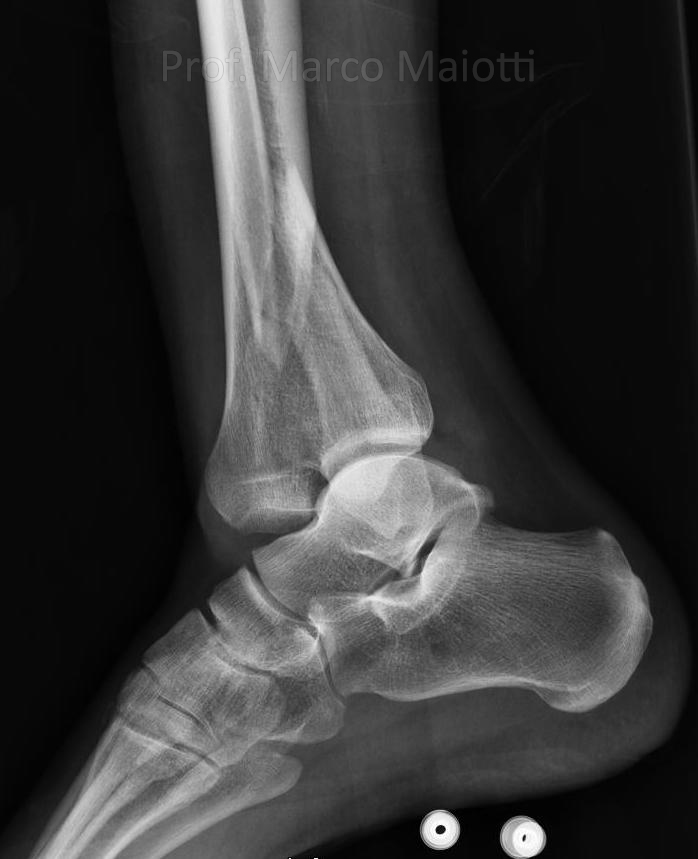

Più rare sono le fratture del pilone tibiale (che spesso coinvolgono anche i malleoli) (Fig.1 – Fig.).

Queste sono fratture molto difficili da affrontare. La caviglia è una regione anatomica coperta solamente da un sottile strato cutaneo. La pelle in questa sede è molto delicata e se non gestita in maniera idonea durante la chirurgia, può andare incontro a disturbi di cicatrizzazione esponendo l’osso sottostante, con conseguente altissimo rischio di infezione. Questo rischio concreto spesso ha dissuaso gli ortopedici da eseguire ricostruzioni chirurgiche nei soggetti vittime di queste fratture, accettando gradi variabili di invalidità funzionale. Oggi fortunatamente grazie a tecniche chirurgiche avanzate anche mini-invasive è possibile eseguire la ricomposizione anatomica di queste gravi lesioni limitando al massimo le possibili complicanze (Fig.3 – Fig.4).